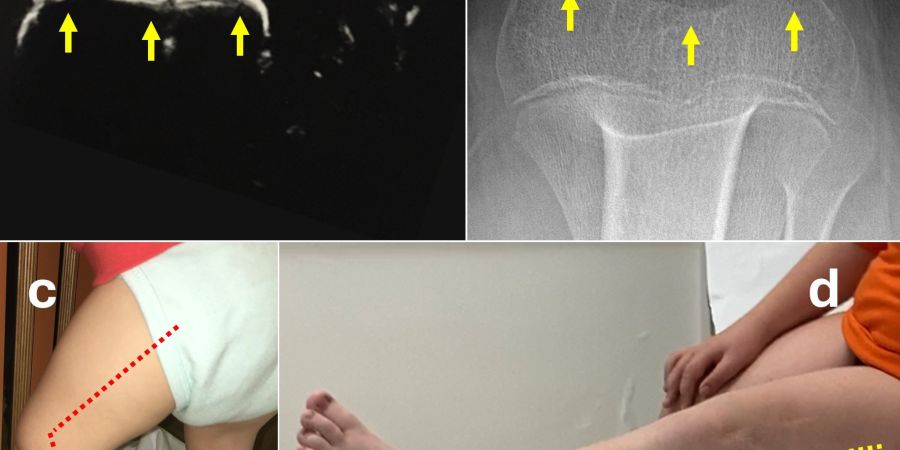

📌 A 9-year-old boy with autism and severe toe walking underwent minimally invasive corrective surgery at our center. The results were maintained over time.